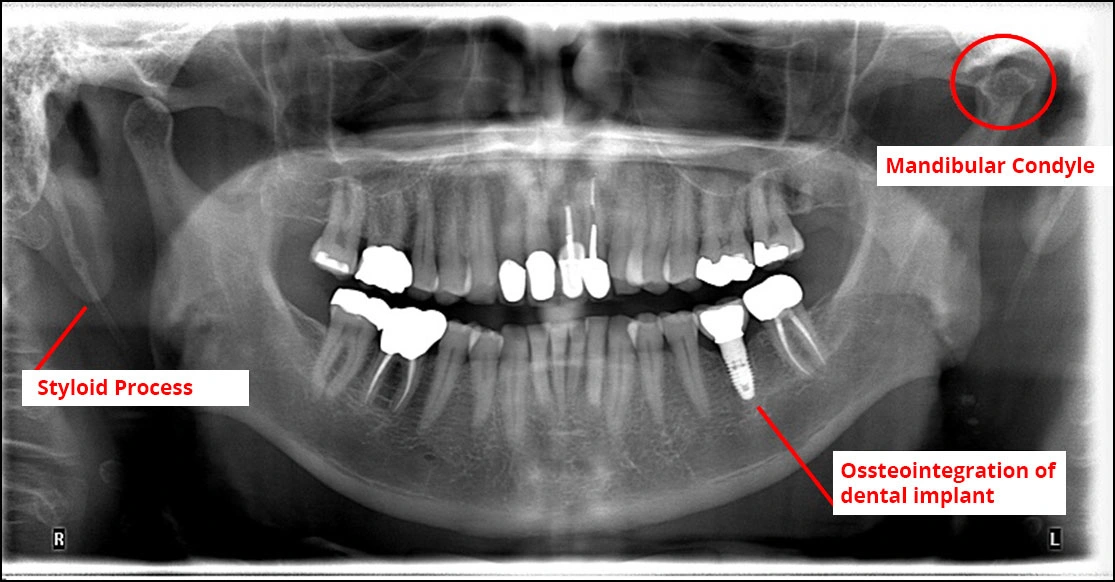

This article outlines key anatomical features identifiable in an opg and illustrates some common pathology. learn about the indications, technique and image evaluation of orthopantomography, a type of panoramic radiograph. learn how to identify key anatomical features and common pathology on an orthopantomogram (opg), a radiograph of. successful interpretation of panoramic radiographs begins with an understanding of the normal anatomy of the head and neck and how it is. orthopantomogram (opg) anatomical landmarks /. normal anatomy on opg. The third molars (wisdom teeth) are unerupted, which can be normal at 20 years (eruption.